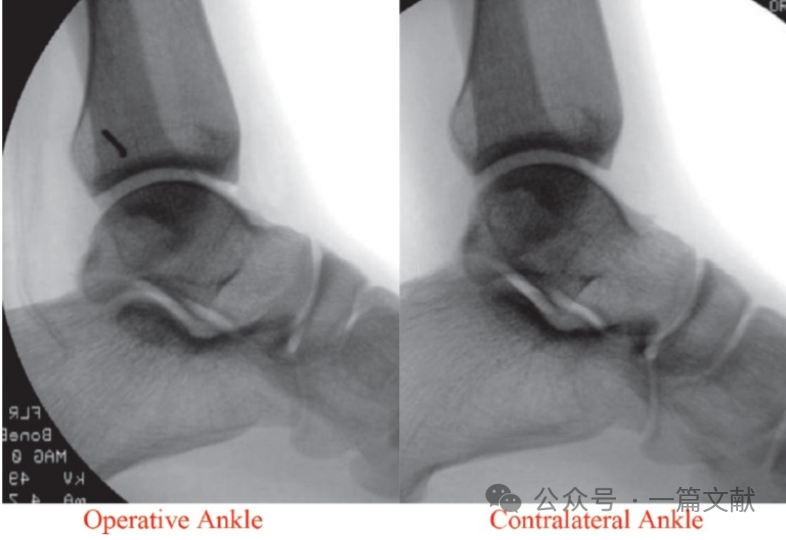

螺钉最终固定的踝穴位片与健侧相对比如下图:

图片